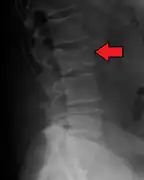

Illustration showing the most common site of bone lesions in vertebrae

Bone pain affects almost 70% of people with multiple myeloma and is the most common symptom.[15] Myeloma bone pain usually involves the spine and ribs, and worsens with activity. Persistent, localized pain may indicate a pathological bone fracture. Involvement of the vertebrae may lead to spinal cord compression or kyphosis. Myeloma bone disease is due to the overexpression of receptor activator for nuclear factor κ B ligand (RANKL) by bone marrow stroma. RANKL activates osteoclasts, which resorb bone. The resultant bone lesions are lytic (cause breakdown) in nature, and are best seen in plain radiographs, which may show "punched-out" resorptive lesions (including the "raindrop" appearance of the skull on radiography). The breakdown of bone also leads to the release of calcium ions into the blood, leading to hypercalcemia and its associated symptoms.

The diagnostic examination of a person with suspected multiple myeloma typically includes a skeletal survey. This is a series of X-rays of the skull, axial skeleton, and proximal long bones. Myeloma activity sometimes appears as "lytic lesions" (with local disappearance of normal bone due to resorption). And on the skull X-ray as "punched-out lesions" (pepper-pot skull). Lesions may also be sclerotic, which is seen as radiodense.[47] Overall, the radiodensity of myeloma is between −30 and 120 Hounsfield units (HU).[48] Magnetic resonance imaging is more sensitive than simple X-rays in the detection of lytic lesions, and may supersede a skeletal survey, especially when vertebral disease is suspected. Occasionally, a CT scan is performed to measure the size of soft-tissue plasmacytomas. Bone scans are typically not of any additional value in the workup of people with myeloma (no new bone formation; lytic lesions not well visualized on bone scan).